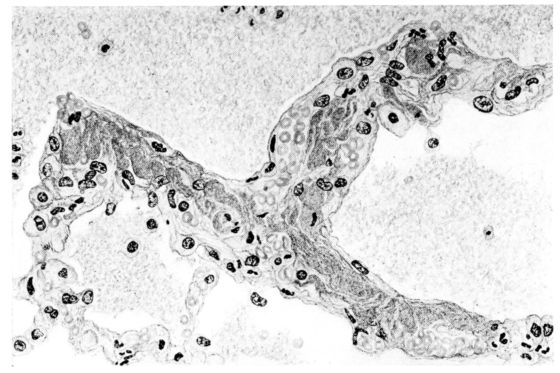

FIG. III. AUTOPSY NO. 90. DRAWING FROM A LESION OF THE TRACHEA (SOMEWHAT OLDER THAN THAT ILLUSTRATED IN FIGURE II). THE MUCOSA IS ENTIRELY LACKING. CONGESTION AND EDEMA ARE THE STRIKING FEATURES IN THE SUBMUCOSA. THE NECROTIZING PROCESS HAS EXTENDED INTO THE MUCUS GLANDS. THIS IS SHOWN IN THE LOWER PICTURE.

FIG. IV. AUTOPSY NO. 205. CONGESTION AND EDEMA OF THE SUBMUCOSA AND REGENERATION OF THE TRACHEAL EPITHELIUM.

The changes are less marked, perhaps, in the trachea than in its finer ramifications. The mucosa is constantly more or less destroyed and large areas, usually focal, are entirely devoid of their epithelial covering. This is replaced by a sparse exudate, composed largely of red blood cells, mucus, a small amount of fibrin, and nuclear fragments (Fig. II). It may dip into the submucosa for a short distance, but usually these indentures are associated with the ducts of the mucous glands into which the inflammatory reaction extends. A more striking feature than the exudate, however, is the edema and the congestion of the submucosa. The loose areolar tissue of the submucosa is spread widely apart, and throughout it distended blood vessels are very conspicuous. Occasionally such a vessel is broken and actual hemorrhage appears in the submucosa. Occasionally, too, the inflammation extends down the duct to the mucous gland itself, and here, also, aplastic inflammatory reaction is evident, inasmuch as the acini now stain intensely red with the cells undifferentiated from each other and specked here and there by broken remains of the dead nuclei (Fig. III). After the disease has continued for a short period, even at the end of five or six days, some regeneration of the epithelial lining may be seen (3) (Fig. IV). But despite this, the acute picture persists, and there goes on, side by side, an attempted repair characterized by epithelial regeneration and the same evidence of acute change. Since the lesion is essentially a superficial one, scars or contractures of any extent are not encountered in the trachea, even in examples of the disease that have ended fatally only after many weeks.[4]